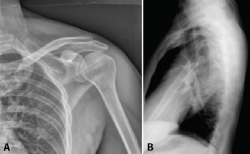

A pesar de ello, debemos solicitar un estudio radiográfico con proyecciones anteroposterior (Grashey), lateral transescapular (‘Y’ de escápula) y axial. Una proyección anteroposterior satisfactoria nos permitirá apreciar la superficie articular de la glenoides con forma de media luna. Una buena proyección lateral en ‘Y’ nos permitirá apreciar la base del acromion orientada posteriormente y la coracoides anteriormente, así como la superposición del ángulo superomedial(9).

Es importante no confundir las variantes de la normalidad, sobre todo en el estudio mediante radiografía simple. Un os acromiale consiste en un fallo de coalescencia de los centros de osificación adyacentes, son bilaterales hasta en un 60% de los casos y se estima que afectan a un 2-3% de la población. El acromion presenta 4 núcleos de osificación: basiacromion, metacromion, mesoacromion y preacromion (Figura 1). El fallo de osificación suele darse más frecuentemente entre meso- y metacromion. Las hipoplasias glenoideas, menos frecuentes, y las líneas epifisarias pueden llevar también a equivocación a la hora de valorar radiográficamente las fracturas de escápula.